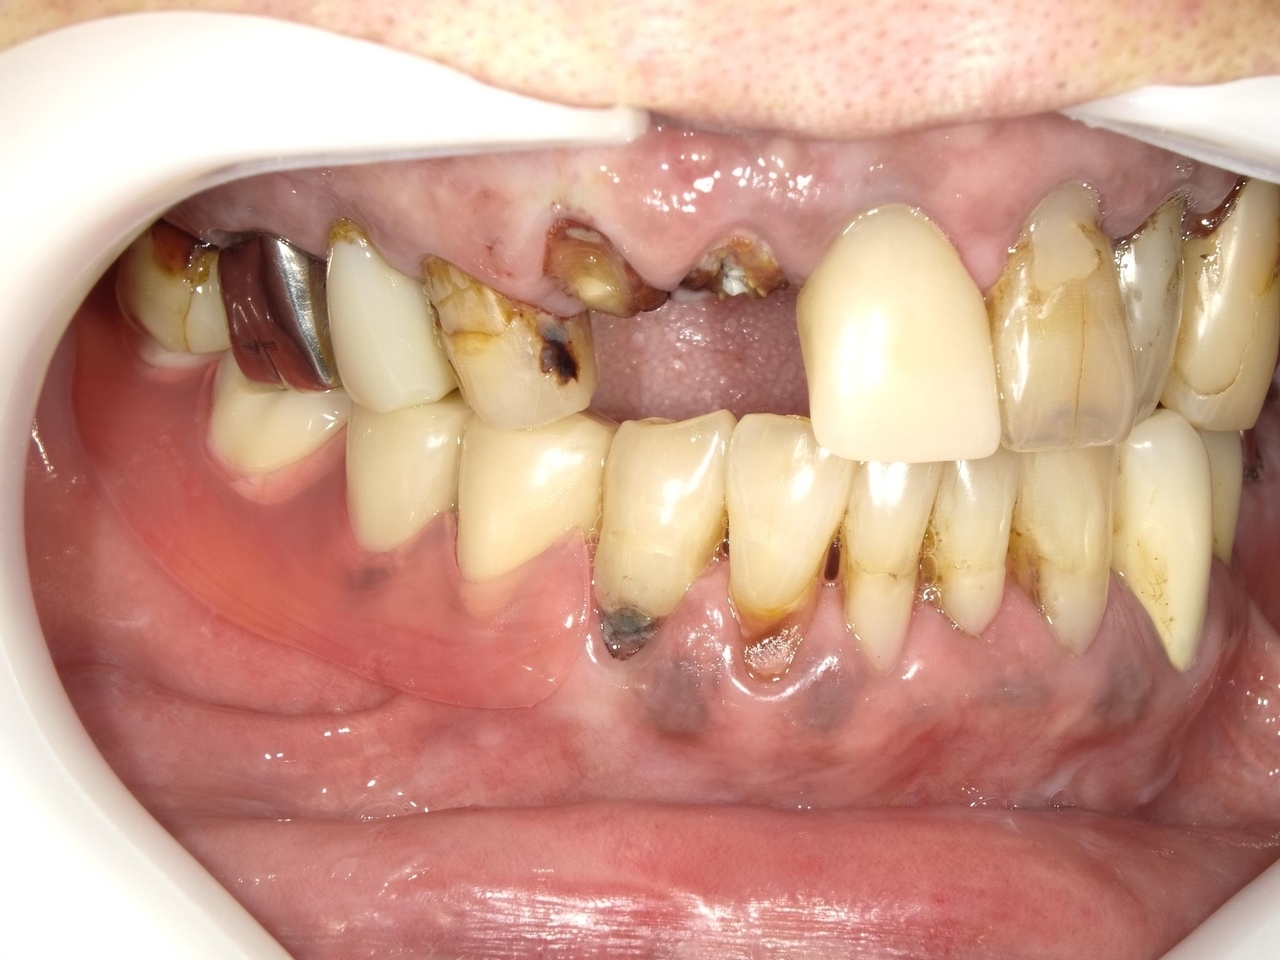

Before

枚方市のインプラントの症例

K・S様 女性 60代

症状としては、 右上4から7番までのすべての歯の著しい動揺があり、食事が困難であった。

治療法としては、患者様は、患者様が3か月以内の治療完了を望んでいたために、炎症が若干あったが、右上4から7番ぼすべての抜歯を行い、右上4番(抜歯即時埋入)、右上6番(上顎洞までの骨がほとんどないため、グラフトレスサイナスリフト施行)にインプラントを1回法で手術を終え、2か月半後にインプラントの状態が安定したために、3か月で上部構造の、右上456のジルコニアブリッジを装着して、治療を終えています。

治療結果としては、抜歯したと同時にインプラントを埋入することで、抜歯した穴が自然に治る過程で、インプラントの骨結合と組織の治癒が同時に行われるために、3か月という治療期間で治療を終了することができたことと、機能面・審美面でも回復を行うができた。また、右上6番に関しては、グラフトレスサイナスリフトを行うことで、従来のサイナスリフトに比べ、約9か月早く治療を終えることができました。

治療の期間・回数:約3か月、インプラント抜歯即時埋入から最終補綴物装着まで8回

治療の価格:792000円(税込)

治療費の内訳:インプラント基本料(フィックスチャー(メガジェンインプラントANYONE使用) 及び手術費用、投薬費用、レントゲン費用、インプラント上部費用(アバットメントおよびジルコニアクラウンの費用用)330000円×2 660000円(税込み)。オプション、抜歯即時埋入加算(人工骨費用を含まず)5500円×2 11000円(税込み)右上5ジル9コニアブリッジのポンテック費用 88000円 右上6グラフトレスサイナスリフト費用 33000円(税込み

治療のリスクや副作用:手術後に、痛みや腫れ、出血、合併症などを引き起こす可能性があります。噛む感覚がご自身の歯と異なる場合があります。見た目がご自身の歯と異なる場合があります。手術後にメインテナンスを継続しないと、インプラントが抜け落ちる可能性があります。